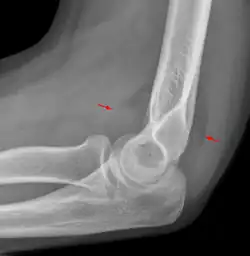

Fat pad sign: Ventral fat pad bowed and dorsal fat pad visible in a case of a nondisplaced fracture of the radius head which is not visible directly.

The fat pad sign, also known as the sail sign, is a potential finding on elbow radiography which suggests a fracture of one or more bones at the elbow. It may indicate an occult fracture that is not directly visible. Its name derives from the fact that it has the shape of a spinnaker (sail).[1] It is caused by displacement of the fat pad around the elbow joint. Both anterior and posterior fat pad signs exist, and both can be found on the same X-ray.

In children, a posterior fat pad sign suggests a condylar fracture of the humerus. In adults it suggests a radial head fracture.

The fat pad sign is invaluable in assessing for the presence of an intra-articular fracture of the elbow. An anterior fat pad is often normal. However a posterior fat pad seen on a lateral x-ray of the elbow is always abnormal. The patient will be unable to flex their elbow and requires orthopaedic input.[2]